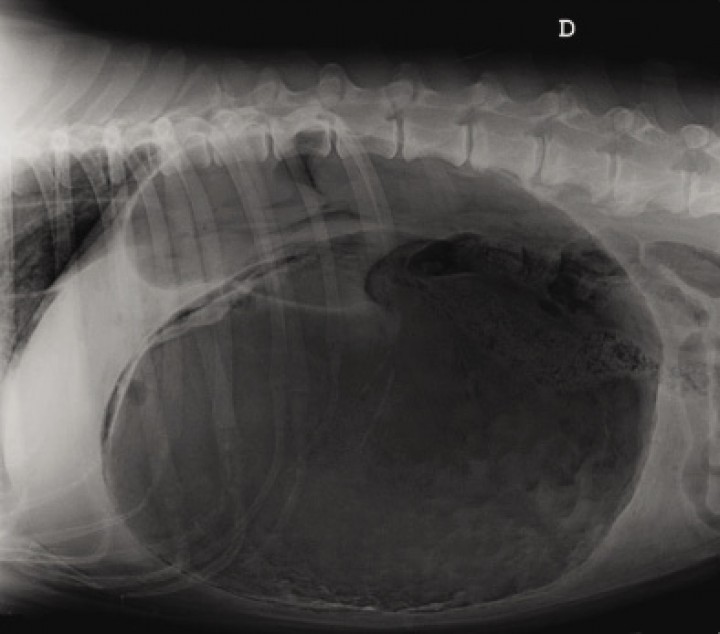

Historia clínica

Mastín, macho castrado, de 7 años de edad y 54 Kg de peso. Acude al servicio de urgencias por decaimiento, vómitos improductivos y distensión abdominal. En la exploración física muestra congestión de membranas mucosas con un tiempo de relleno capilar superior a 2 segundos, taquicardia con pulso femoral muy débil, taquipnea y leve hipotermia (36 ºC). Se realizó una radiografía lateral de la cavidad abdominal (Fig. 1).

<p>Radiografía lateral derecha de la cavidad abdominal. Mastín, macho castrado de 7 años de edad y 54 Kg de peso, que se presenta con vómitos improductivos y distensión abdominal.</p>

Figura 1

Radiografía lateral derecha de la cavidad abdominal. Mastín, macho castrado de 7 años de edad y 54 Kg de peso, que se presenta con vómitos improductivos y distensión abdominal.